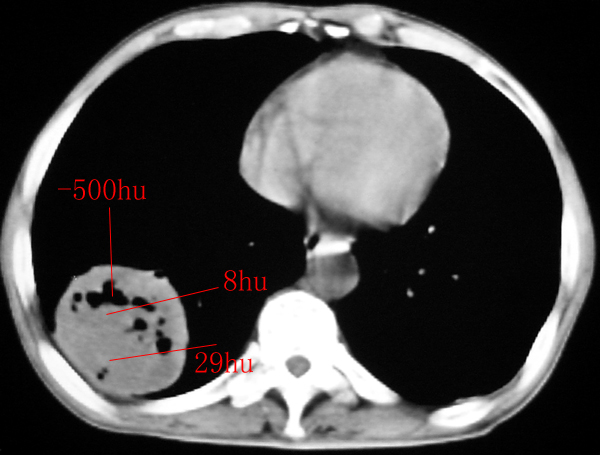

我认为本例肿块内为坏死组织与实性组织混在一起,并夹杂有极低密度气体影,加上肺肿边缘部分呈不规则浅分叶,应该诊断为周围型肺癌。

患者三个月前的ct增强片也显示肿块壁不规则并有明确的壁结节,也支持周围型肺癌的诊断。

右下肺占位性病变,其边缘较光整无明显分叶,似有包膜,邻近胸膜无凹陷征及牵拉征象,包块内见数个大小不等气液面及不规则透亮影,纵隔未见明显淋巴结肿大。结合上次ct检查,考虑:炎性包块或真菌感染包块可能性大,周围型肺癌可能性小。

感谢楼主反馈结果。囊实性肿块,壁厚薄不均,壁结节有明显强化,均支持肺癌诊断。